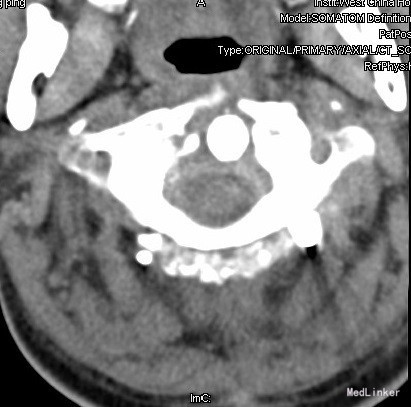

查体:查体:T:36.7oC,P:80次/分,R:20次/分,BP:137/82mmHg。神志清楚,无病容,皮肤巩膜无黄染,全身浅表淋巴结未见肿大。。颈静脉正常。心界正常,心律齐,各瓣膜区未闻及杂音。胸廓未见异常,双肺叩诊呈清音,双肺呼吸音清,未闻及干湿啰音及胸膜摩擦音。腹部外形正常,全腹柔软,无压痛及反跳痛,腹部未触及包块,肝脏肋下未触及,脾脏肋下未触及,双肾未触及。双下肢无水肿。视:平车推入病房,颈椎颈托围领固定,颈部、前额部及全身皮肤未见皮损及异常。触:颈1-4棘突及椎旁明显压痛、叩击痛,感觉正常,四肢肌张力正常。动量:颈椎活动受限,尤以旋转受限为重。双侧肱二头肌反射、肱三头肌反射、膝反射正常,双侧babinski征阴性,右侧Hoffmann征阳性、左侧阴性。 辅助检查:颈椎X线片、MRI、CT提示:寰椎椎板前弓骨折,寰枢关节旋转半脱位

诊断:1.陈旧性寰枢关节旋转脱位2.陈旧性寰椎前弓骨折 治疗:全麻下行:行经前路寰枢椎脱位切开撬拨复位+经后路寰枢椎侧块螺钉内固定、去髂骨后外侧植骨融合术